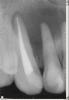

kenig Опубликовано 18 октября, 2012 Поделиться Опубликовано 18 октября, 2012 (изменено) Июль 12г.Жалобы:постоянный привкус гноя во рту, по утрам под губой белый сгусток, каждые три дня распухает небо, при нажатии на небо выделяется гной в области 12 зуба.Объективно:11 зуб покрыт исскуственной коронкой, 12 временная реставрация (находится на этапе лечения), 13 зуб интактный. В области 12 зуба с вестибулярной стороны свищ.R-гр.: киста вобласти 11,12,13 зубов.Анамнез: 12 зуб лечат год в другом лечебном учреждении, безуспешно, ничего не меняется.Рекомендовано:КТ верхней челюстиЭндо-лечение 11,12,13 зубов. Проведено лечение 11 зуба-коффердам, хлорка, лимонка, каласепт на две недели,пломбирование-вертикалка. Результат-пациент счастлив-привкус гноя пропал, под губой по утрам ничего нет, распухает раз внеделю. Свищ на месте. Проведено лечение 13 зуба-коффердам, хлорка, лимонка,каласепт на две недели, пломбирование-вертикалка. Все это время 12 зуб моем, моем,но из него все время льется, хотя через 10-20 минут мытья его возможно высушить.Результат-еще лучше, распухает раз в две недели. Свищ на месте..Сентябрь-наконец-то принесли КТ-ужас. В процессе небный корень 14 зуба, хотя реагирует на холод как витальный зуб. Небно нет кости от 11 до 14 зуба, в области 11 зуба сообщение с полостью носа. Вопросы:Эндо 14 зубу проводить? Реагирует на холод, как живой.12 зуб пломбировать? Просушить его возможно через минут 10-20 мытья. Временные промежутки между обострениями увеличиваются, но меня результат не радует.Как бы поступили Вы в такой клинической ситуации? -диагностический 12 зуба-контрольный 11 зуба-контрольный 13 зуба-КТ 11 зуба-КТ 12 зуба-КТ 13 зуба-КТ 14 зуба был подобный случай, причинный был 22, эндо с апексификацией 22, гидроокись не приносила ожидаемых результатов, раз 5 получал несколько 2-кубовых шприца желтой опалесцирующей жидкости, потом высушил, запаковал МТА, хоирург сделал декомпрессию по парч, полтора года мыли хлоргексидином раз в 2 недели, вот что получилось, без всякой хирургии Изменено 18 октября, 2012 пользователем kenig 1 Ссылка на комментарий